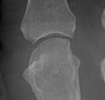

Radiographic Appearance:

Calcium deposition is often seen at the triangular fibrocartilage of the wrist.

Subchondral sclerosis, joint space narrowing, subchondral cyst formations

which may be quite large, and intraarticular bodies from subchondral osseous

collapse and fragmentation are all findings which can be seen in patient's

with CPPD disease. These radiographic abnormalities are most common at the

radiocarpal articulation and at the 2nd and 3rd metacarpophalangeal joints.